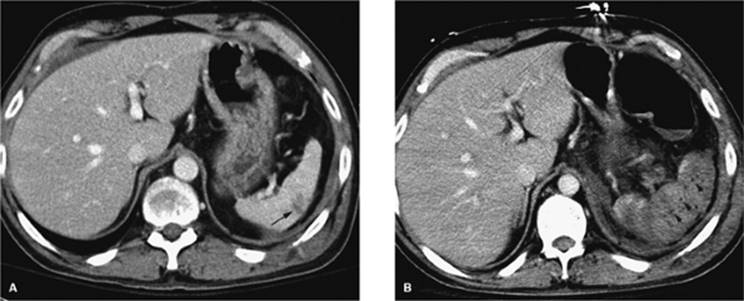

Figure 35.4. CT-guided drainage of infrahepatic abscess. A: CT scan through the fluid collection (asterisk) with localizer grid applied on the skin over the target. B: Following determination of pathway, entry site marking, sterile skin prep and drape, and local anesthesia the access needle is advanced under CT guidance into the fluid collection. Repeat CT is performed to evaluate needle path and depth (arrow). C: Postdrainage obtained at the same level as A shows loop of drainage catheter (short arrow) in markedly decompressed abscess cavity. (Case courtesy of Lauren Alexander, MD, Gainesville, FL.)